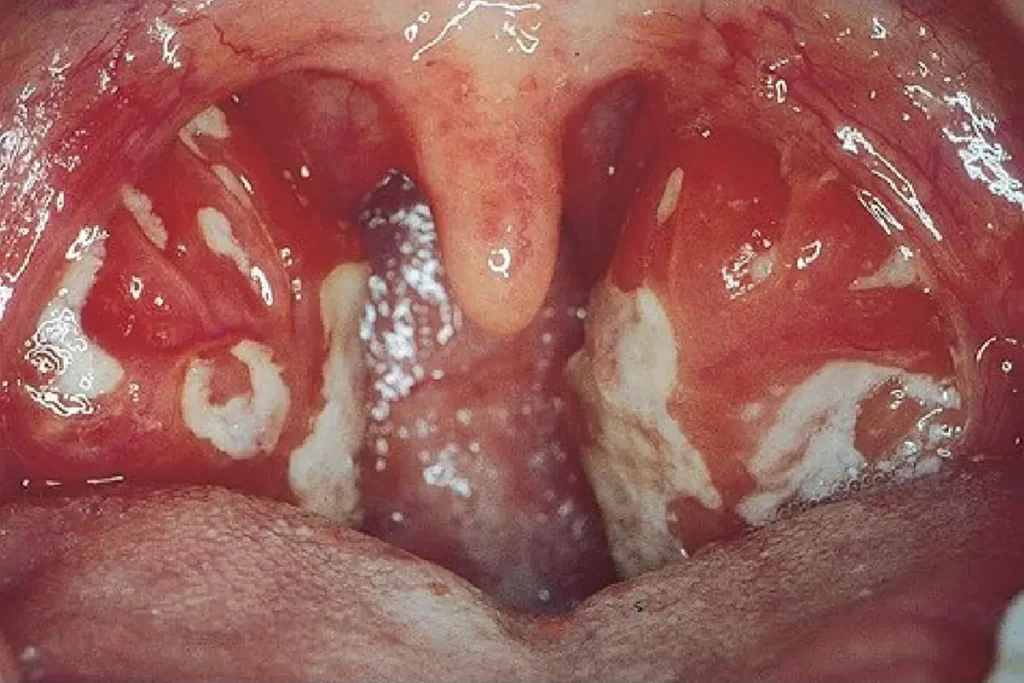

- Halsschmerzen , oft mit Mandelschwellung

- Geschwollene Lymphknoten , vor allem im Halsbereich

- Halsschmerzen

- Geschwollene Lymphknoten